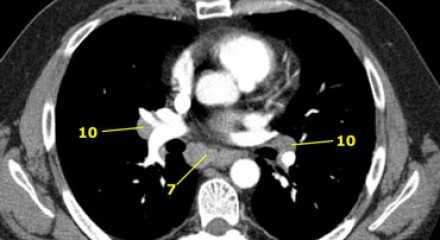

На изображении слева 3А узел в преваскулярном пространстве. Обратите внимание так же на ниже расположенные паратрахеальные узлы справа относящиеся к 4R группе.

7. Подкаринальные лимфатические узлы

Эти лимфатические узлы расположены ниже уровня бифуркации трахеи (карины), но не относятся к нижнедолевым бронху и артерии. Справа они располагаются каудальнее нижней стенки промежуточного бронха. Слева они располагаются каудальнее верхней стенки нижнедолевого бронха. Слева лимфатический узел 7 группы справа от пищевода.